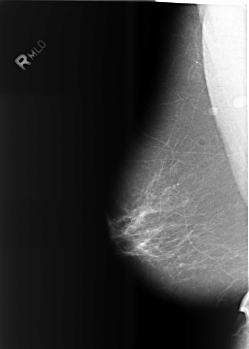

B_3466_1.LEFT_MLO

RIGHT_MLO LINES 5576 PIXELS_PER_LINE 3984 BITS_PER_PIXEL 12 RESOLUTION 50 NON_OVERLAY